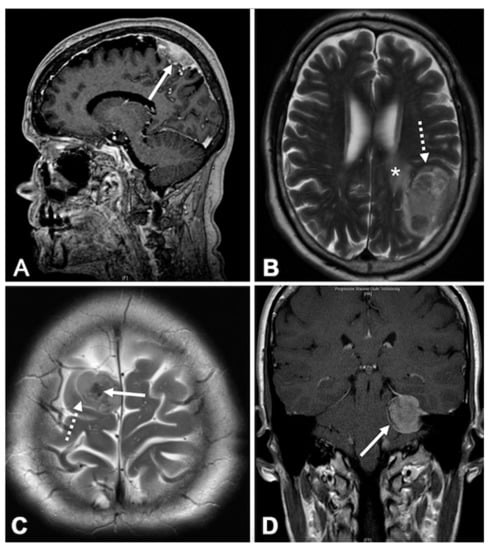

2.4. Vessel Fibrosis is Associated with Morphological Characteristics on MRI